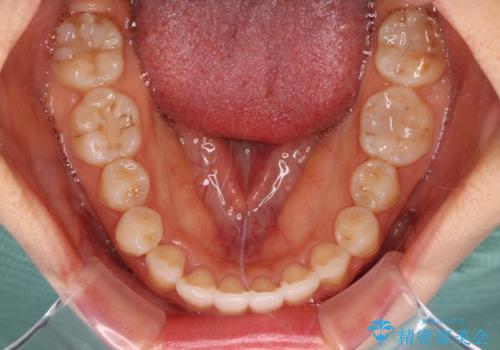

- 飛び出した前歯と口元の突出感を気にして来院された患者様です。

奥歯の咬み合わせを見ると、上顎が下顎に対して相対的に前方にありました。

口元の突出感を改善するためには、上顎臼歯を後方に移動させた咬み合わせにする必要があります。

インビザライン単体で改善することも可能ですが、達成する可能性が高くないため、カリエールディスタライザーという補助装置を併用して、より確実性を上げることとしました。

奥歯の咬み合わせを改善しながら、並行してインビザラインで歯列を整えることとしました。